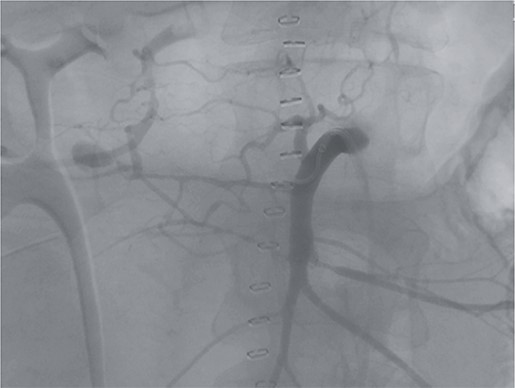

Postoperatively, the patient achieved hemodynamic stabilization in the intensive care unit. On the sixth postoperative day, there was a recurrence of circulatory collapse in addition to relevant bloody discharge through the drains. CT imaging once again revealed an active bleeding of the pancreaticoduodenal artery, which was successfully treated interventionally using coiling (Figs 2 and 3).

Postinterventional angiography, showing the aneurysm of the pancreaticoduodenal arcade, after interventional coiling.